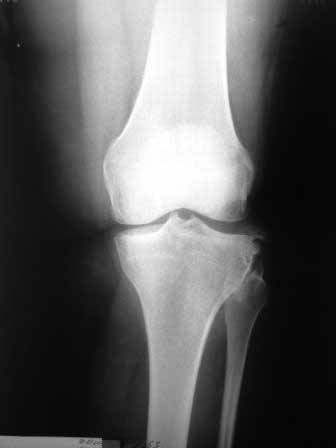

Сегодня на приеме была больная 27 лет, вес 120кг. Травма 7 лет назад - ДТП. Была ЧМТ, двухсторонний перелом пилона, обширные рваные раны бедер, голеней. Судя по нынешней картине - вывих левой голени.

Ходит практически не хромая, жалобы на неустойчивость голени при ходьбе. При стресс тестах - грубейшая несостоятельность связочного аппаратаколенного сустава. Хотелось бы услышать мнение о целесообразности пластического восстановления связок после столь длительного периоданестабильности сустава.С уважением,Leonid m

У пациентки застарелый разрыв наружной боковой связки. Нестабильность вскоре приведет к деф артрозу коленного сутсава, к тому же избыточный конституциональный вес. Делайте пластику наружной боковой связки.

Сделайте МРТ. При таком р-гене возможен разрыв задне-латерального комплекса с выраженной нестабильностью. Тактика - пластика ЗКС, ЛКС.